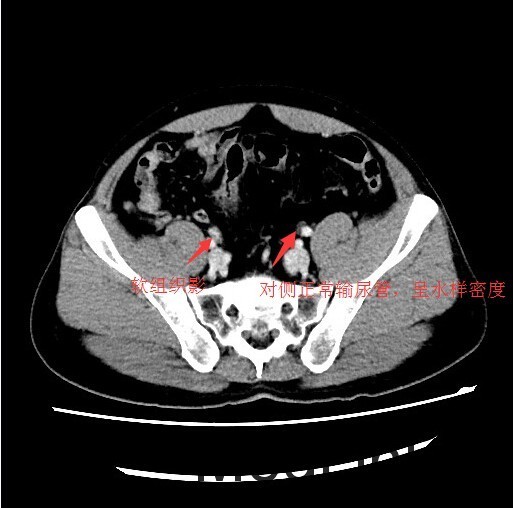

查体:肛门括约肌稍松弛,前列腺明显增大,大小约:4×3cm,表面光滑,质韧,边缘清楚,中央沟变浅,未触及明显结节,指套未见染血。 辅查:CT示:右侧输尿管下段软组织肿块影,考虑输尿管癌可能,相应输尿管中上段、右肾肾盂扩张积水

讨论:输尿管恶性肿瘤多来源于输尿管上皮组织,以移行细胞癌最常见,移行细胞癌多呈乳头状生长,突入腔内,约1/3为多发性肿瘤。影像表现为输尿管、肾盂和肾盏不同程度扩张积水,并于输尿管梗阻端发现软组织肿块或腔内有充盈缺损,增强扫描轻中度强化,集合临床表现,多可作出诊断,不过应注意输尿管癌的多发性,勿漏诊!